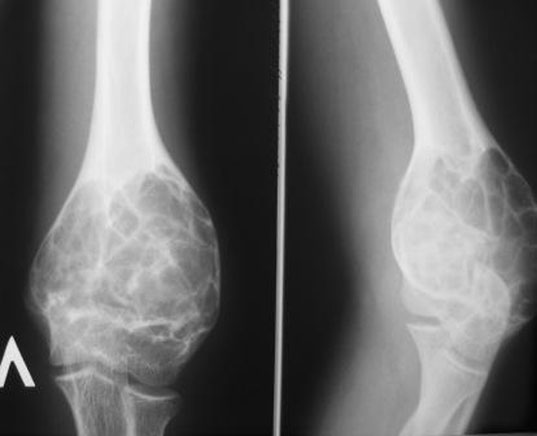

Остеосаркома коленного сустава: информация и поддержка

Раздел: Необычные решения